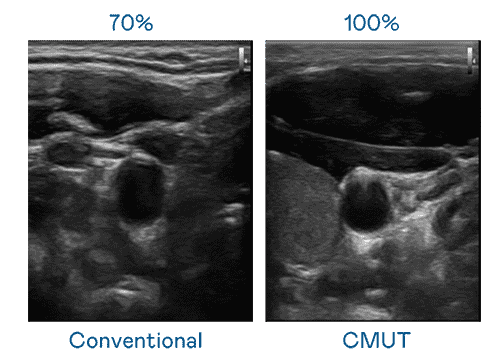

CMUT 技术是一种用电容式微机电元件来产生超音波讯号的技术。。。与传统 PZT 压电式技术相比,,CMUT 频宽增加 30%,,,更宽频的超音波讯号让影像解析度大幅提升,,,是实现高影像品质医疗超音波扫描、、、、促进精准医疗发展的关键技术。。。。

大频宽带来超清晰影像

超音波影像的解析度高低,,首先取决于探头能发出的讯号频宽。。。尊龙集团 CMUT 可提供高清晰的超音波讯号,,,,提供高频宽、、、、高灵敏度、、影像纹理细节更高的超音波影像,,,,协助医护人员缩短影像判读时间及利用精准的医疗影像进行诊断。。